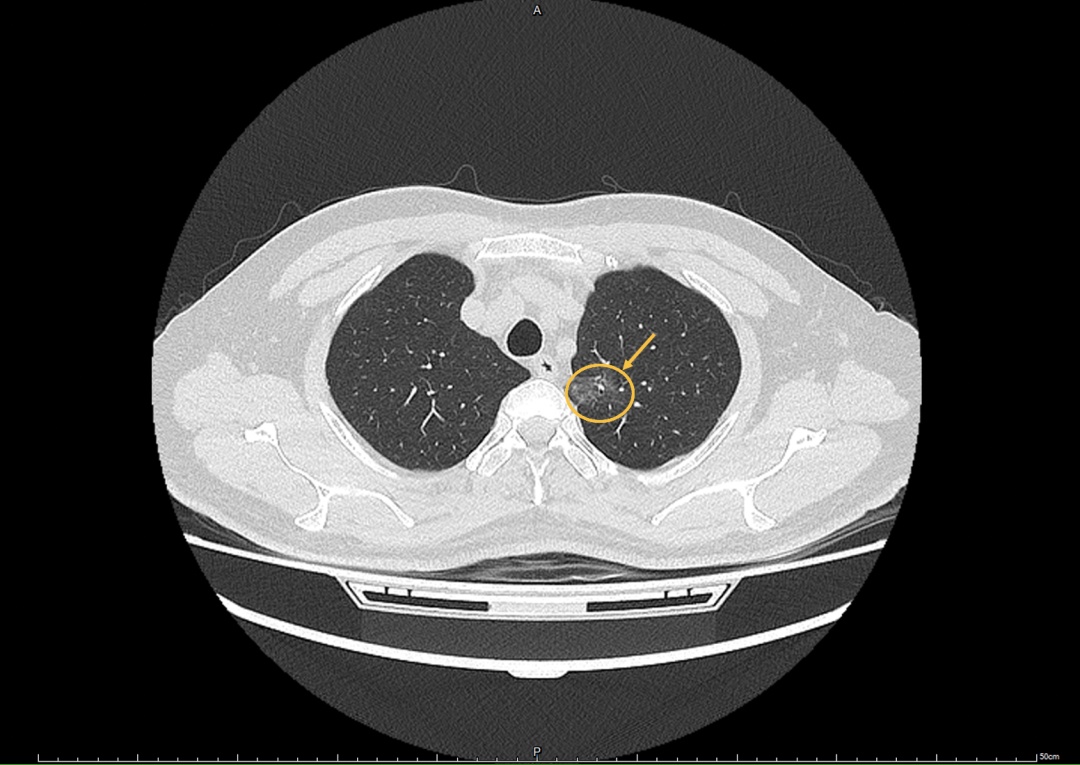

几个月前,一份体检报告打破了老章平静的生活。报告上“肺部结节,建议进一步检查”的字样,让老章着实紧张了一把。火急火燎地在当地医院进一步检查后,医生考虑早期肺癌可能性比较大,建议尽快通过微创手术予以切除。

随后,胸外科韩丁培和陈凯两位医生顺利完成了单孔胸腔镜微创手术,通过侧胸壁3cm的小切口,通过鼓肺-萎陷法清晰地显示出尖后段的边界,切除了患者左肺上叶结节所在尖后段。在胸外科、麻醉科、手术护士等多方默契配合下,使困难插管对手术的影响降到了最低。术后的老张情况平稳,考虑到他还有呼吸暂停综合征,回到病房后护士对他进行了严密监护;麻醉科还周全地准备了鼻插管,以备不时之需。

最终,病理结果提示老章切下的肺结节是肺部腺癌,但好在手术及时,淋巴结尚未转移,只要定期随访复查,长期生存率很高。这让老章心里的大石头终于落了地,满满的劫后余生之感让这个高大的汉子泪流满面。